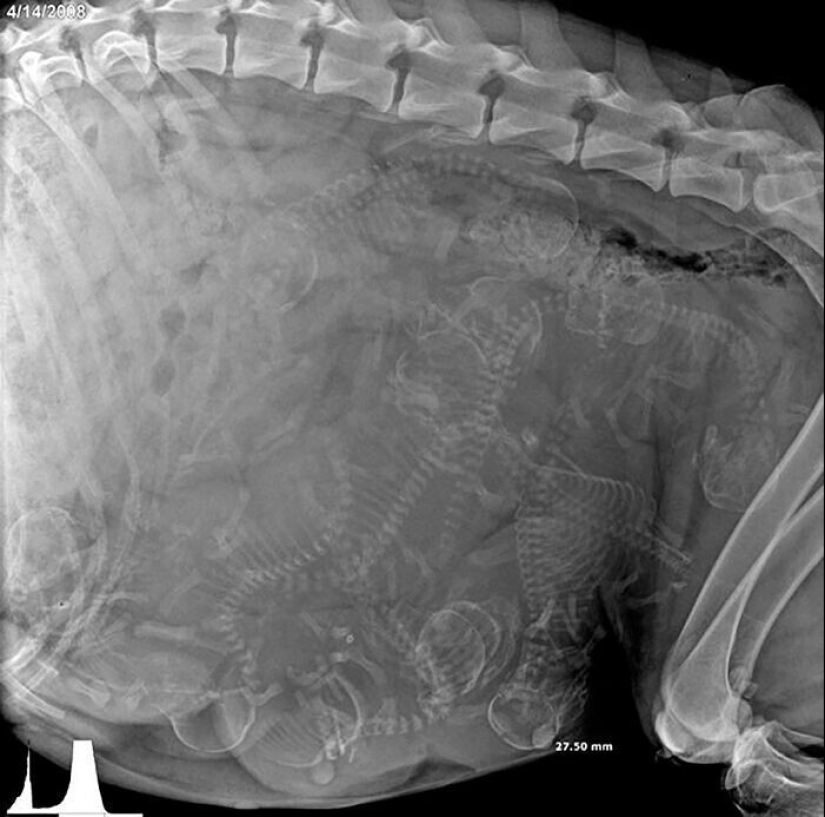

Ultrasound image of a pregnant dog